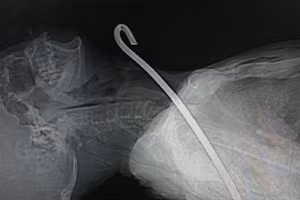

GD&TĐ - 5 trong số những bệnh nhân bị ngộ độc hiện đang được cấp cứu tại Khoa Cấp cứu chống độc (Bệnh viện Đa khoa tỉnh Hà Tĩnh). Các bác sĩ vẫn đang tiếp tục theo dõi và điều trị những trường hợp này.